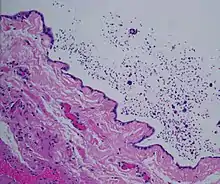

| Ultrasound of a testicle (grey) and a spermatocele (black). | |